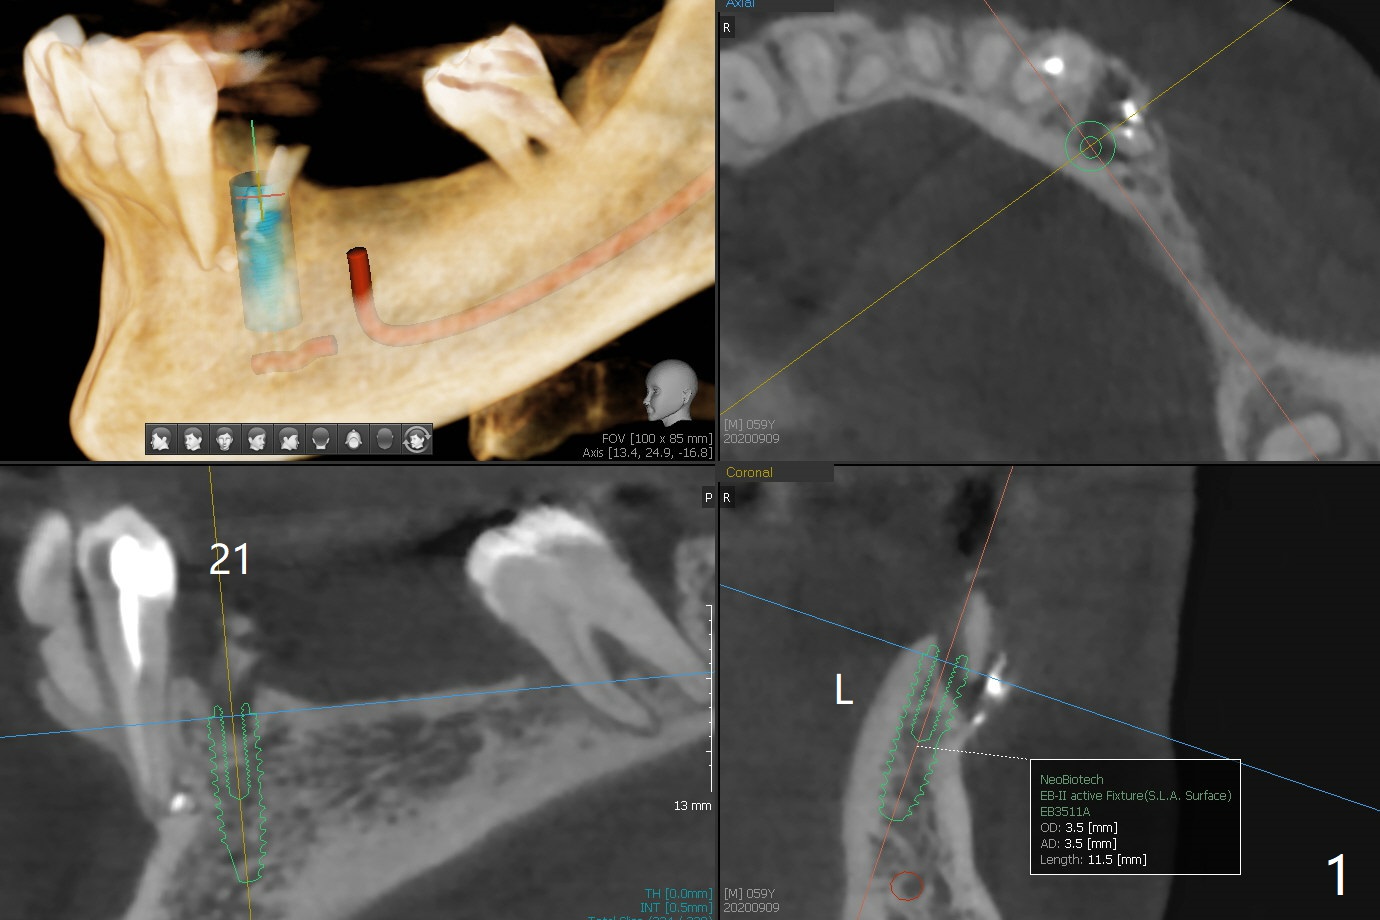

A 59-year-old woman has an abscess buccal to #21 (residual root), immediate placement being imminent, while the teeth #19 and 20 have been missing for a while. Since the ridge is narrow even at #21, three narrow implants will be placed at these sites (Fig.1-3). Please place an implant as close to the lingual (L) plate (but not to touch it to avoid deviation during placement) at #21 (Fig.1).